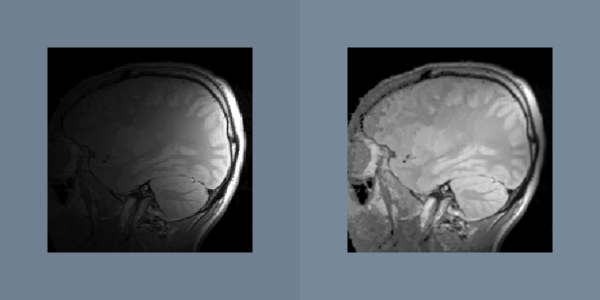

- src/PythonicAPI/ImageProcessing/Attenuation.md 6 additions, 0 deletionssrc/PythonicAPI/ImageProcessing/Attenuation.md

- src/PythonicAPI/ImageProcessing/Attenuation.py 143 additions, 0 deletionssrc/PythonicAPI/ImageProcessing/Attenuation.py

- src/Testing/Baseline/PythonicAPI/ImageProcessing/TestAttenuation.png 3 additions, 0 deletions.../Baseline/PythonicAPI/ImageProcessing/TestAttenuation.png